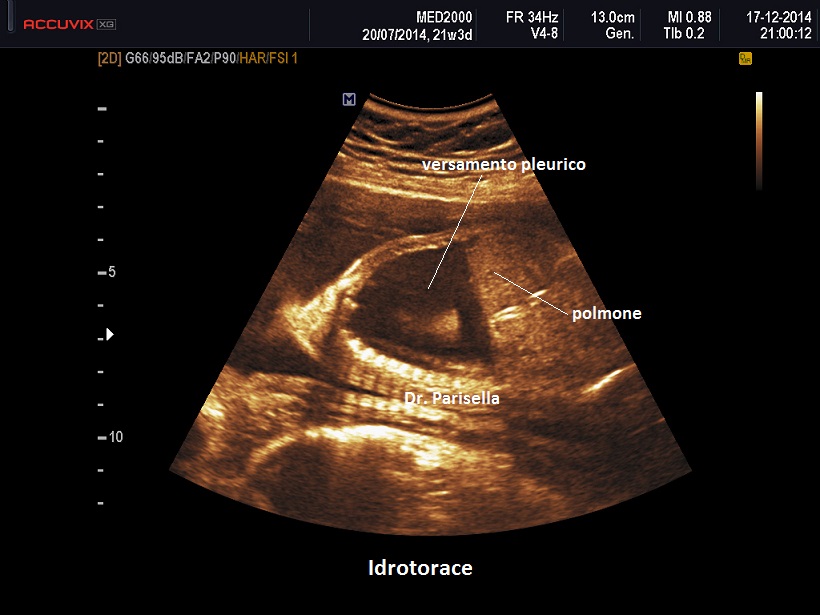

Diagnosi Ecografica

La diagnosi ecografica non offre in genere difficoltà ed è rappresentata da un versamento pleurico monolaterale o bilaterale.

Nelle forme monolaterali si ha shift mediastinico con dislocazione controlaterale del cuore.